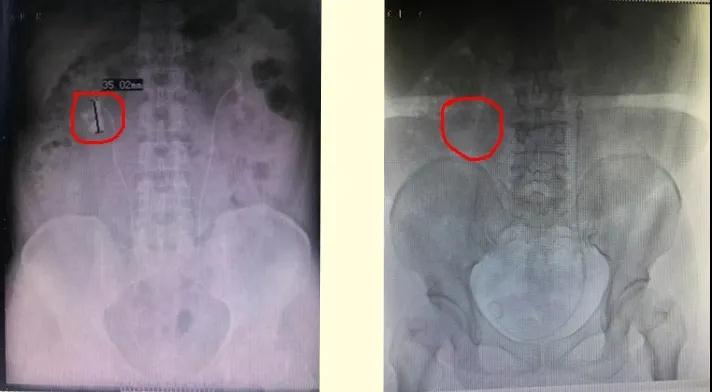

张先生结石属于鹿角形结石又叫铸型结石,结石负荷巨大,且曾经做过开刀手术,若采用双侧经皮肾镜碎石取石术手术,难度大、风险高、肾脏损害大。蒋小雷带领全科室成员积极探讨手术方式,最终决定采用目前国内最先进的智能控压清石系统输尿管软镜钬激光碎石术。经过两小时努力,顺利将张先生体内结石清理完毕。

8月10日,泌尿外科门诊来了一位面色难堪,走路扶腰的女性患者。检查发现,这位胥女士为左肾及输尿管结石、急性肾功不全、脓毒血症。原来是“小小的石头”折磨着她的左腰反复剧烈疼痛。保肾大战,一触即发。蒋小雷决定先对胥女士进行抗感染治疗,再实施手术清理结石。